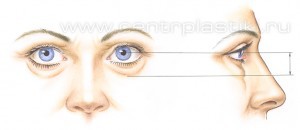

Это глубоко ошибочное мнение – современную пластическую операцию на веках, ни в коем случае, нельзя считать простой операцией. Хирургические методики блефаропластики (пластики век) в настоящее время развились (как самолетостроение) и стали значительно более сложными по сравнению с традиционным удалением “избытков кожи и жира”, которое выполнялось раньше всем пациентам подряд. В основном, это связано с тем, что в последние годы случилась, по-сути, революция во взглядах и подходах пластических хирургов к омоложению век – за последние два десятилетия было детально описано анатомическое строение этих областей лица и механизм их старения. Что привело пластических хирургов во всем мире к изменению техники выполнения омолаживающих операций на веках. Так, еще несколько десятилетий назад удаление кожи, мышцы, и жировой клетчатки, всем пациентам подряд, при стандартной блефаропластике (пластике век), которую выполняли многие пластические хирурги, зачастую приводило и приводит к неудовлетворительным результатам – вызывая западения век и придавая векам возрастной или «трупный» вид (Рис. 1-2)

Рис. 1. Нормально стареющие нижние веки